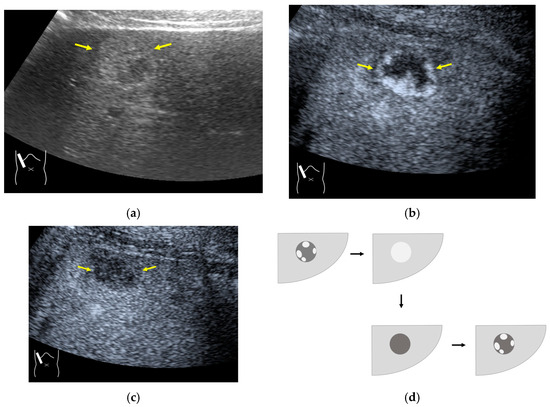

The image frame rate (the number of times/second) is a characteristic of US examinations, and it is closely related to the temporal resolution. The higher the frame rate, the faster the image movement [30,31], which allows for rapid survey scans of the target lesion [32]. Meanwhile, the number of US beam lines is generally related to the spatial resolution. The smaller the number of US beams, the faster the scanning speed. However, this can compromise the US image quality (Figure 1a,b). Thus, it is important to balance the frame rate and the image quality in US examinations. Another way to increase the frame rate is to reduce the image width, i.e., narrowing the view angle. This method can be easily performed even with middle-price CEUS machines (Figure 1c). Thus, there are two ways to gain high-frame rate CEUS images using current CEUS machines: (a) narrowing the frame angle (as shown in Figure 1c) and (b) decreasing the number of US beams. The former keeps the same spatial resolution and is suitable for observing small lesions. The latter is only available with high-end CEUS machines and is suitable for observing relatively large lesions.

Figure 1.

A schematic drawing of high-frame-rate CEUS: (a) narrowing the viewing angle; (b) decreasing the number of ultrasound beams; (c) representative CEUS image of the method (a,c): frame rate 12/s; (d): frame rate 30/s (focal nodular hyperplasia, arrows). A more detailed vascular structure (in this case, it has a spoke-wheel appearance) can be displayed using high-frame-rate CEUS when observing hypervascular mass lesions.

The current high-end machines have the above two functions. By selecting function (b), the machine automatically decreases the number of US beams (usually to half of the usual number) and increases the frame rate (usually to twice the usual rate) without changing the width of the field of view. This function is especially useful when observing the vascular structures of high-flow liver tumors.